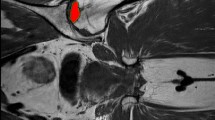

For PNV, a failure rate of 13 % was observed with a PNV of less than 2500 mm3, 55 % with a PNV between 2500 and 5000 mm3 and 69.2 % with a PNV greater than 5000 mm3. Documentation of a typical case with pre-/postoperative X-rays and MRIs is given in Fig. 5.

a Preoperative X-ray and b MRI images of a study patient with a large defect (14,261 mm3) on the right side and a relatively small defect on the left side (1139 mm3). c After advanced core decompression, MRI shows a remaining necrotic volume of 10,864 mm3 on the right side and 140 mm3 on the left side. d In the further follow-up, the patient suffered from a collapse of the femoral head on the right side, whereas the left side was pain-free